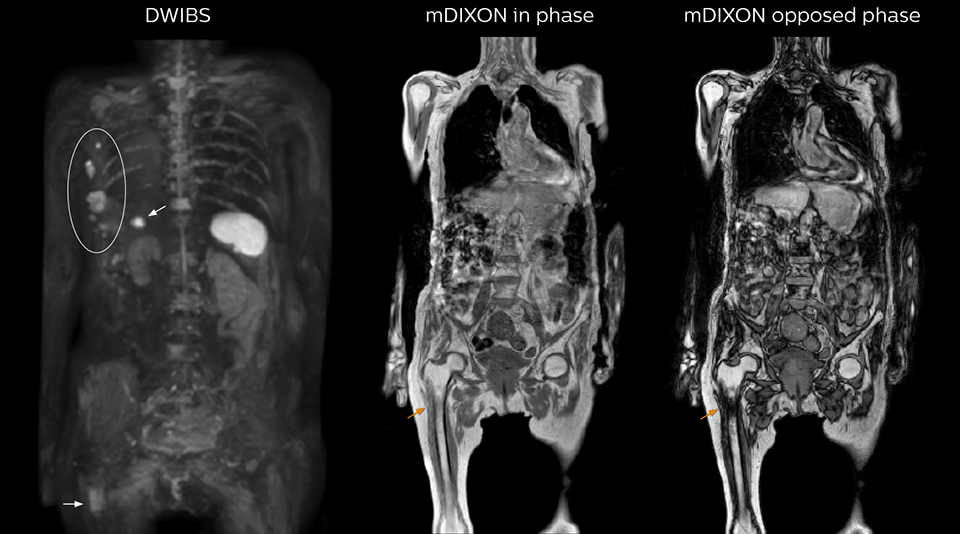

“The DWIBS sequence’s value in oncology cases is due to the high contrast it creates between lesions and surrounding tissue. Whole body DWI is requested by physicians who need to clarify TNM staging or determine therapeutic strategies, oncologists in need of diagnosis or follow-up scans, surgeons who need to see the presence of distant lesions that are sometimes difficult to detect by CT before surgery, and urologists for the evaluation of bone lesions, and the effect of chemotherapy and radiotherapy.”

“When we limited the scan coverage to the area from neck to femur, we could fit more clinical information in approximately the same scan time. So, we added coronal mDIXON, sagittal T1-weighted, and sagittal STIR sequences to our examination, instead of performing only axial DWIBS and coronal single-shot TSE scans.” The single shot T2-weighted TSE images are used for morphology and compared to DWIBS images to identify T2 shine-through. Sagittal STIR images are used in patients with inflammation or bone metastasis.

“mDIXON FFE allows us to quickly get information we need to assess the presence of fat. That gives us more information when we need to diagnose bone lesions, and when we are asked to judge fat-containing lesions such as hepatocellular or renal carcinoma,” Dr. Nobusawa says. “The mDIXON fat images can help us to differentiate fatty bone marrow from bone lesions. This is especially useful in elderly people, who tend to have fattier bone marrow. The water images provide a high signal-to-noise ratio in the intestinal canal, which is valuable for visualizing lesions in the colon,” he says.

Kawasaki Sawai Hospital’s whole body protocol also includes an mDIXON FFE sequence. Because mDIXON provides images for four contrast types – water only, fat only, in-phase and out-of-phase – from a single acquisition, it is useful in many ways.

“In-phase and out-phase sagittal T1-weighted FFE images help us to visualize and further characterize bone lesions such as metastasis and bone-marrow hyperplasia that have high signal on DWI. These images are also used throughout radiotherapy, to monitor changes in the fatty bone marrow.”